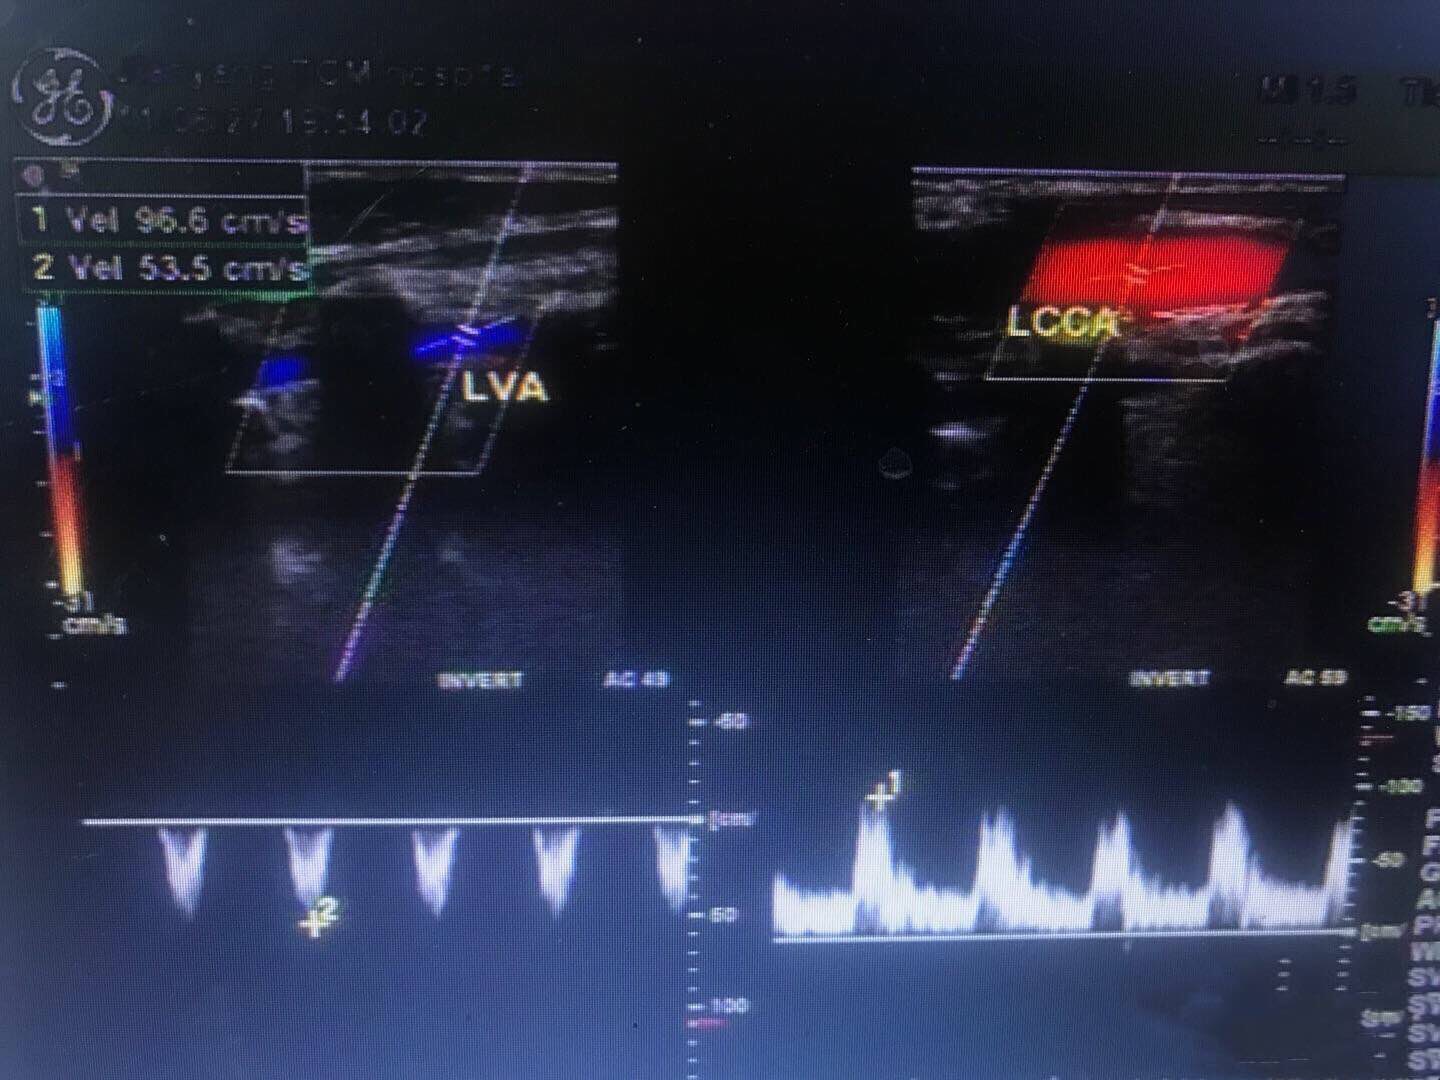

左侧桡动脉血流频谱,为低阻单相波形。左侧椎动脉和左侧颈总动脉血流,二者血流方向相反。 右侧和左侧锁骨下动脉起始部,左侧明显较右侧管径细。